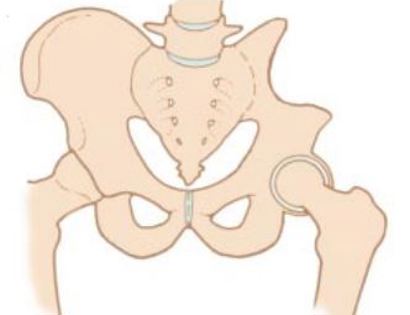

Removal of tumor and reconstruction. Once the tumor is removed the bone and joint are restored (reconstructed) if the tumor involved the “ball and socket” region. A “cup” may be utilized to replace the acetabulum if it was removed during surgery.